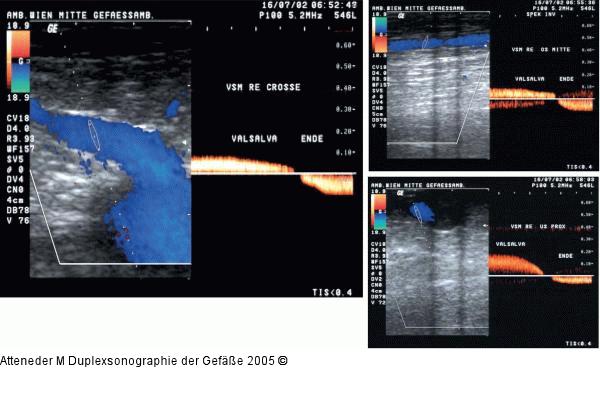

Abbildung 14: Duplexsonographie - V. saphena Dopplerkurven (Flußumkehr bei Valsalvamanöver) einer insuffizienten V. saphena magna, abgeleitet im Bereich der Crosse, der Oberschenkelmitte und des Unterschenkels |

Abbildung 14: Duplexsonographie - V. saphena

Dopplerkurven (Flußumkehr bei Valsalvamanöver) einer insuffizienten V. saphena magna, abgeleitet im Bereich der Crosse, der Oberschenkelmitte und des Unterschenkels |